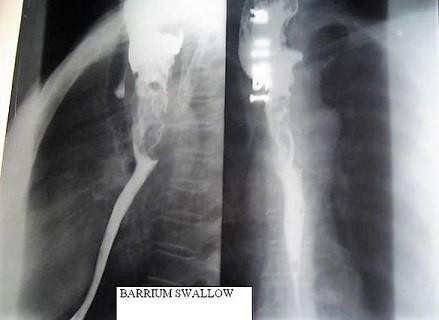

Barium-Schluck

In this test you drink some barium liquid. The barium liquid is often fruit-flavoured so it is pleasant to drink. You stand in front of an X-ray machine whilst X-ray pictures are taken as you swallow. This test aims to look for problems in the gullet.

These include a narrowing (stricture), hiatus hernias, tumours, reflux from the stomach, disorders of swallowing, etc. You will usually be asked not to eat or drink for a few hours before this test. A barium swallow test takes about 10 minutes.

Barium swallow X-ray

By Netha Hussain (Own work) via Wikimedia Commons